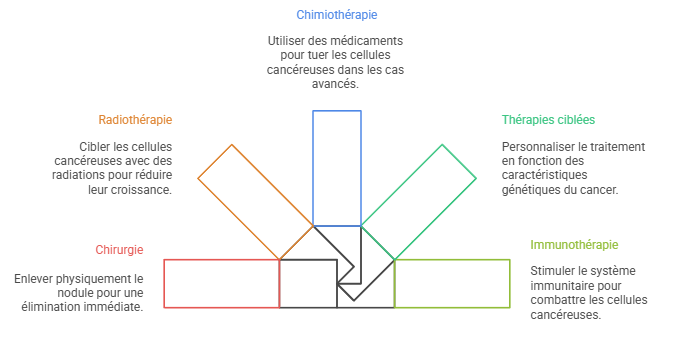

Lorsqu’un nodule est suspecté d’être malin, des interventions plus actives peuvent être nécessaires. Les options thérapeutiques comprennent :

- La chirurgie pour retirer le nodule

- La radiothérapie ciblée

- La chimiothérapie dans les cas avancés

- Les thérapies ciblées basées sur les caractéristiques génétiques du cancer

- L’immunothérapie pour stimuler le système immunitaire contre les cellules cancéreuses

Il est important de souligner que le traitement est personnalisé en fonction de nombreux facteurs, notamment l’âge, l’état de santé général, les préférences personnelles et le type spécifique de nodule. Une communication ouverte avec votre équipe médicale est essentielle pour prendre des décisions éclairées concernant votre traitement.